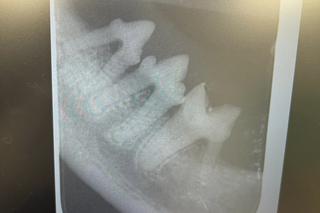

Zoe to uroczy kociak, który trafił do Centrum Adopcyjnego Lecznicy Ada w Przemyślu. Zanim jednak zwierzęta trafią do nowego domu, muszą przejść badania i leczenie, gdy tego wymagają. Zoe potrzebował sanacji zębów, gdyż bez tego zmagałby się ze stanami zapalnymi. Teraz spokojnie może szukać nowego domu.

Sanacja jamy ustnej albo to najczęściej przeprowadzany zespół czynności stomatologicznych u małych zwierząt jakim jest kociak Zoe. Proces sanacji to w pierwszej kolejności dokładne zbadanie jamy ustnej. Większość kotów, które mieszkają  w naszych domach zmaga się z chorobami przyzębienia. Dbanie o higienę i czystość zębów u naszych pupili to rzecz bardzo trudna, a profilaktyka i kontrola nad płytki bakteryjnej jest bardzo ważna. Zaniedbanie zębów  u kota może spowodować  bolesne stany zapalne. Dlatego sanacja zębów była niezbędna u Zoe. Podczas tego zabiegu weterynarze nie tylko pozbyli się płytki i osadów nazębnych, ale też zadbano, by kotek nie miał problemów z próchnicą. Teraz futrzak zaczeka na nowy dom, gdzie trafi już wolny od wszelakich uszczerbków na zdrowiu.